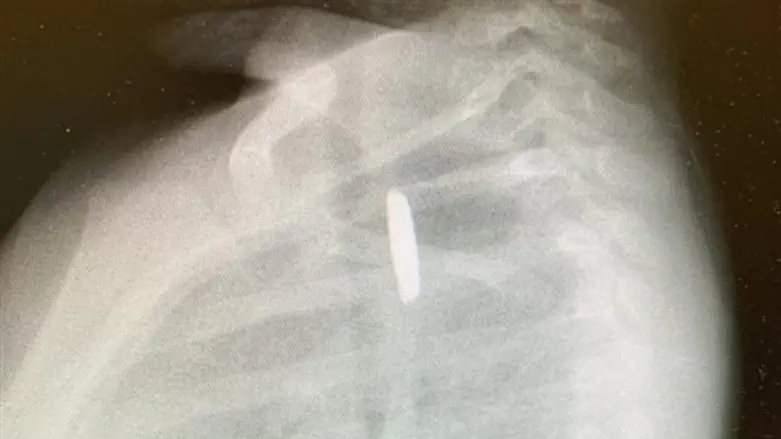

הפעוט סבל במשך שישה שבועות מהקאות חוזרות ונשנות, ורק לאחר תקופה זו בוצע לו צילום חזה, בו התברר כי בטריה עגולה (בטריית כפתור) תקועה בתוך הוושט שלו.

במשך חודש וחצי לקחה האם את בנה לרופא בקהילה, למוקד ולבית חולים אחר, ורק אחרי שהתעקשה לבצע צילום חזה לבנה הקטן, התגלתה בטריה בתוך הוושט שלו.